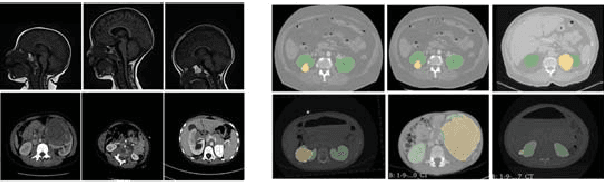

Abstract:Due to a high heterogeneity in pose and size and to a limited number of available data, segmentation of pediatric images is challenging for deep learning methods. In this work, we propose a new CNN architecture that is pose and scale invariant thanks to the use of Spatial Transformer Network (STN). Our architecture is composed of three sequential modules that are estimated together during training: (i) a regression module to estimate a similarity matrix to normalize the input image to a reference one; (ii) a differentiable module to find the region of interest to segment; (iii) a segmentation module, based on the popular UNet architecture, to delineate the object. Unlike the original UNet, which strives to learn a complex mapping, including pose and scale variations, from a finite training dataset, our segmentation module learns a simpler mapping focusing on images with normalized pose and size. Furthermore, the use of an automatic bounding box detection through STN allows saving time and especially memory, while keeping similar performance. We test the proposed method in kidney and renal tumor segmentation on abdominal pediatric CT scanners. Results indicate that the estimated STN homogenization of size and pose accelerates the segmentation (25h), compared to standard data-augmentation (33h), while obtaining a similar quality for the kidney (88.01\% of Dice score) and improving the renal tumor delineation (from 85.52\% to 87.12\%).